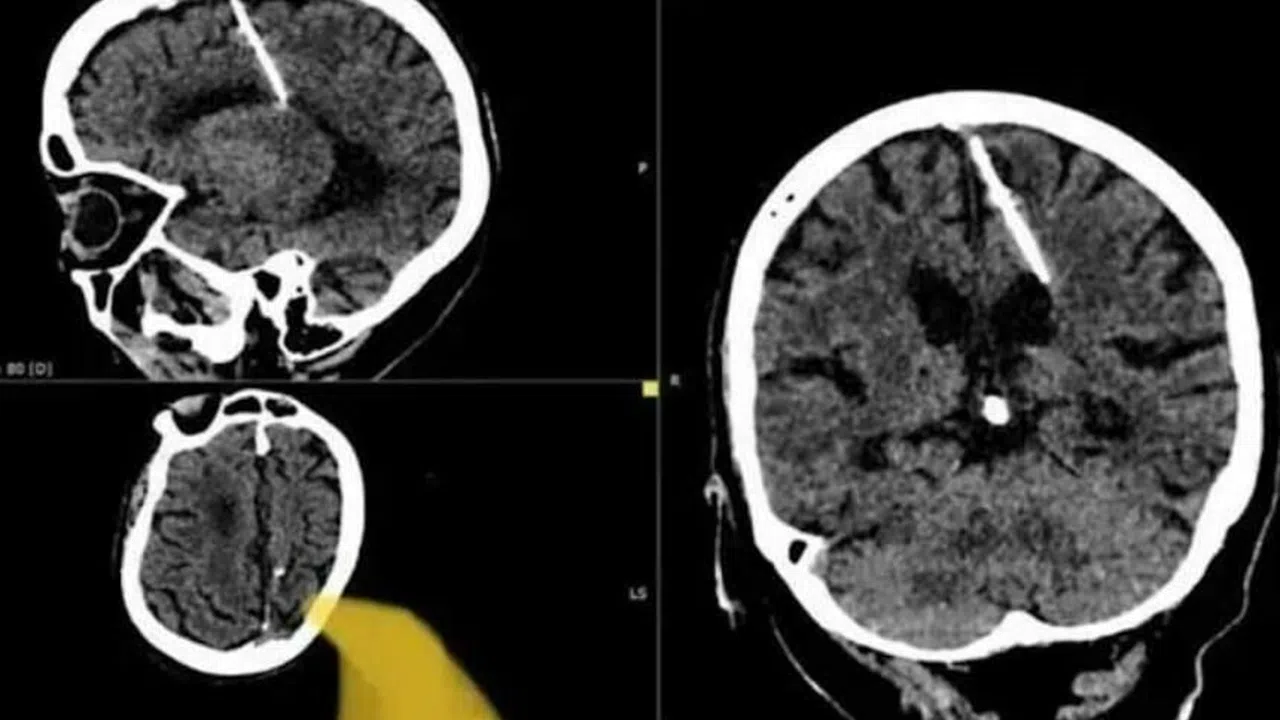

Rusya'nın doğusundaki yaşlı bir kadının, beyninde 3 cm uzunluğunda bir iğne ile 80 yıl boyunca yaşadığı, doktorların tarafından ortaya çıkarıldı.

Rusya'nın doğusundaki bir 80 yaşındaki kadının beyninde 3 cm uzunluğunda bir iğne taşıdığı, bu ilginç durumun doktorlar tarafından keşfedildiği ortaya çıktı. Kadının bu olaya nasıl maruz kaldığı ise dikkat çekici bir hikayeye dayanıyor.

Sakhalin bölgesi sağlık yetkilileri, kadının ebeveynleri tarafından gerçekleştirilen başarısız bir çocuk düşürme girişimi sonucu bu durumun ortaya çıkmış olabileceğini düşünüyor. Bu trajik dönemde Sovyetler Birliği'nde gıda kıtlığı yaygınken, birçok insan zorlu ekonomik koşullar altında yaşıyordu.

Sağlık departmanı yetkilileri, "İğne sol parietal lobuna girdi, ancak amaçlanan etkiyi yaratmadı; kız hayatta kaldı" dedi. Hastanın şaşırtıcı bir şekilde iğnenin neden olduğu bir baş ağrısından veya başka bir sağlık sorunundan şikayet etmediği belirtildi. Durumu şu an ilgili bir doktor tarafından yakından izleniyor.